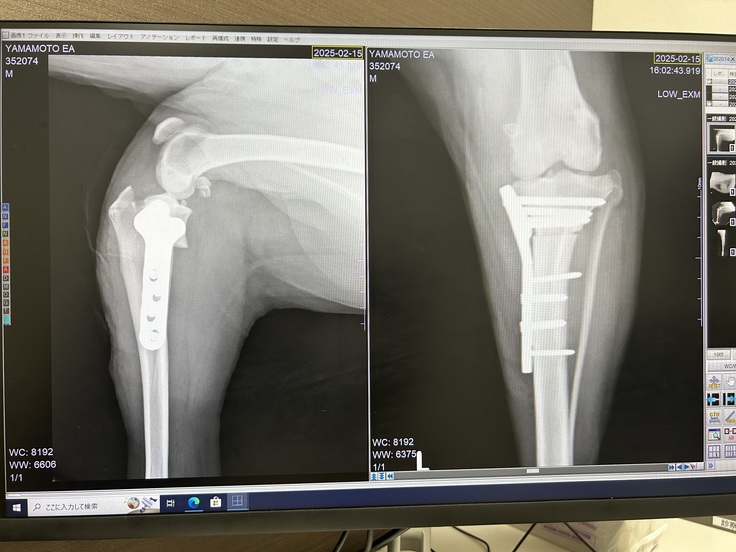

エアは盲導犬協会より1歳からキャリアチェンジ犬として譲り受け、現在10歳を迎えております。先日、滑って転んでしまい、膝前十字靭帯の断裂をしてしまいました。TPLOという手術を受けましたが,長引くリハビリの中今後の治療費にも不安を抱えており、ご支援を賜りたくクラウドファンディングに挑戦いたしました。ぜひご協力よろしくお願いします。

TPLO(脛骨高平部水平化骨切り術)と言う治療を行いました。高額な費用と長期にわたるリハビリが必要となります。

TPLO手術を実施。現在は経過観察中。

今までの治療費:79万円(TPLO脛骨高平部水平化骨切術費用および入院費など)

2025年2月12日〜2025年2月18日

※治療内容や治療費、治療期間は動物病院の確認が取れています。すでに無事に手術は終了しておりますが、経過観察のため週に一度程度通院しております